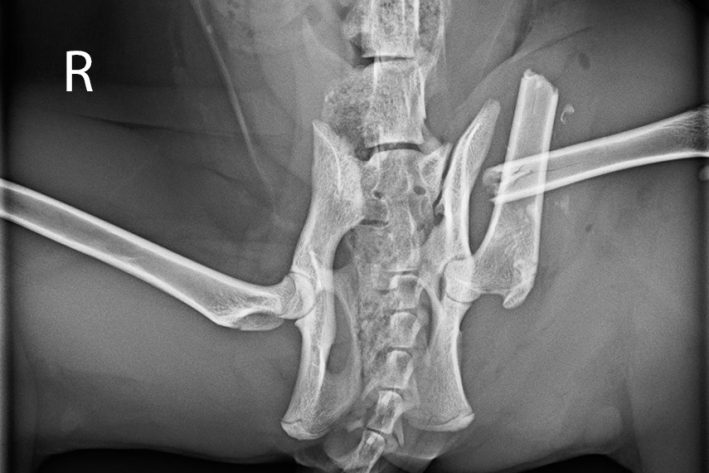

Trümmerfraktur bei einer Katze

Femurfraktur links bei einer Katze